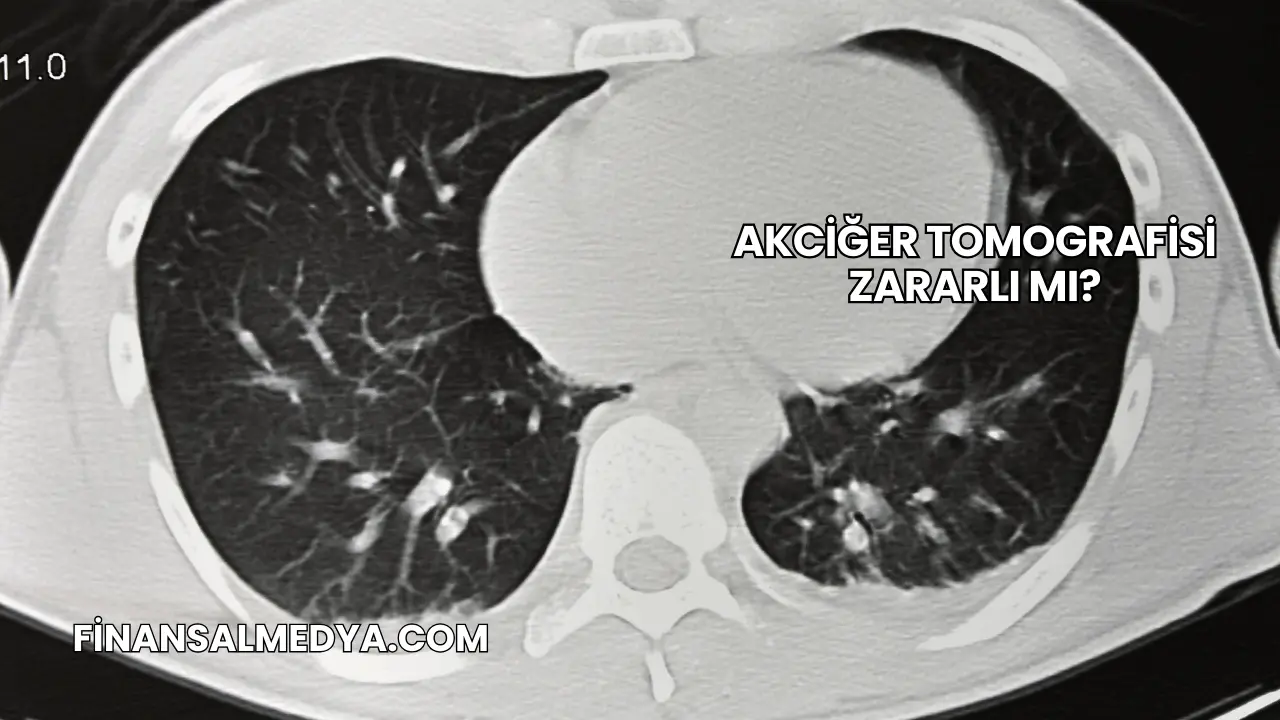

Akciğer tomografisi, akciğerlerde meydana gelen yapısal değişiklikleri görüntülemek için kullanılan gelişmiş bir radyolojik yöntemdir. İnce kesitler alarak detaylı görüntü elde eden bu yöntem, doktorların doğru teşhis koymasına yardımcı olur.

Akciğer tomografisi, özellikle akciğer kanseri, zatürre, tüberküloz ve damar tıkanıklıkları gibi hastalıkların erken teşhisinde kullanılan önemli bir görüntüleme yöntemidir. Kullanıcılar arasında en çok merak edilen nokta ise akciğer tomografisinin zararlı olup olmadığıdır. Bu yazıda akciğer tomografisi ile ilgili detayları, zarar ihtimalini, hangi durumlarda gerekli olduğunu ve dikkat edilmesi gereken noktaları inceleyeceğiz.